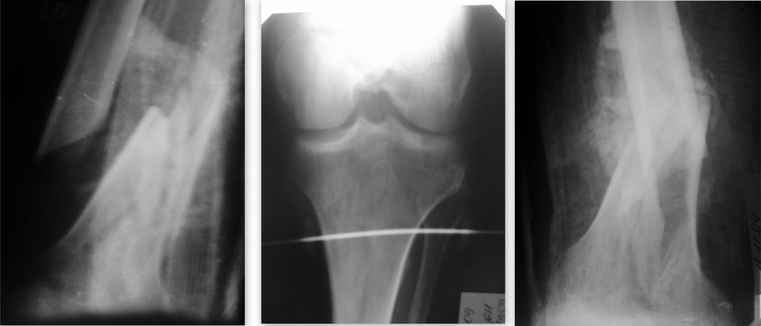

Тяжелая сочетанная травма от 25.09.09 (падение с 5-го эт. в АО У б-го Тяжелая сочетанная травма от 25.09.09 Ушиб г\мозга. З\оскольчатый внутрисуставной перелом л\бедра в н\3. О\оскольчатый внутрисуставной перелом п\бедра в н\3. Медиальный перелом шейки п\бедра. Перелом лонной и седалищной костей справа. Кахексичен, в жизни алкоголизируется. В данный момент ЧМТ невелирована до энцэфалопатии смешанного генеза. Больной доступен продуктивному контакту. Пролежни разрешились. Рана открытого перелома п\бедра зажила 1-м натяжением. Анализы нормализовались. Правая н\конечность сейчас в укороченной гипсовой (циркулярной) повязке. На следующей неделе собираюсь синтезировать левое бедро опорной мыщелковой пластиной с УС. Уважаемые коллеги! Предоставляю данный случай на обсуждение. С уважением А.М.

Искренне извиняюсь коллеги! Представленные Р-граммы - это снимки планируемого левого бедра от 11.11.09